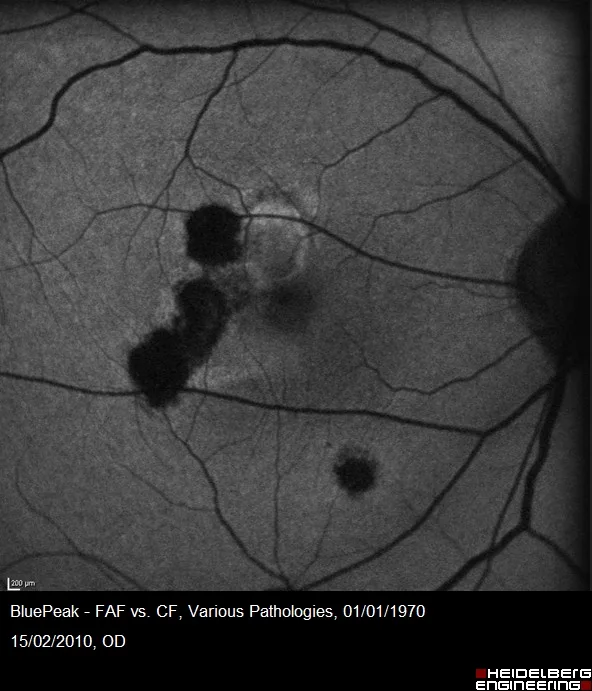

Analyse de la papille

Un scan radial de 24 lignes haute défintion est utilisé pour les mesures de la tête du nerf optique(ONH).

La détection automatisée du BMO et de l’ILM aux 48 points autour de l’ONH permet une analyse précise de l’anneau neurorétinien(ANR).

Les résultats sont comparés à la base normative – représentés avec la classification de Garway-Heath(inféro-nasal, inféro-temporal, temporal, supéro-temporal, supéro-nasal et nasal) – pour permettre une meilleure corrélation entre structure et fonction.

Elle est facilitée par la présentation en centiles.